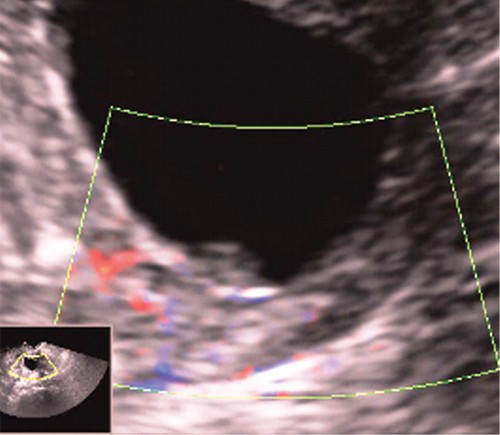

В то же время эхонегативное изображение жидкости (слизи) подчеркивает контуры эхопозитивного патологического образования, делая его хорошо заметным на эхограмме. Поскольку полип имеет внутрипросветный рост и частично обтурирует цервикальный канал, выше или ниже его может скапливаться слизь, что облегчает обнаружение патологического образования (рис. 2).

Рис. 2. Полип в просвете цервикального канала.